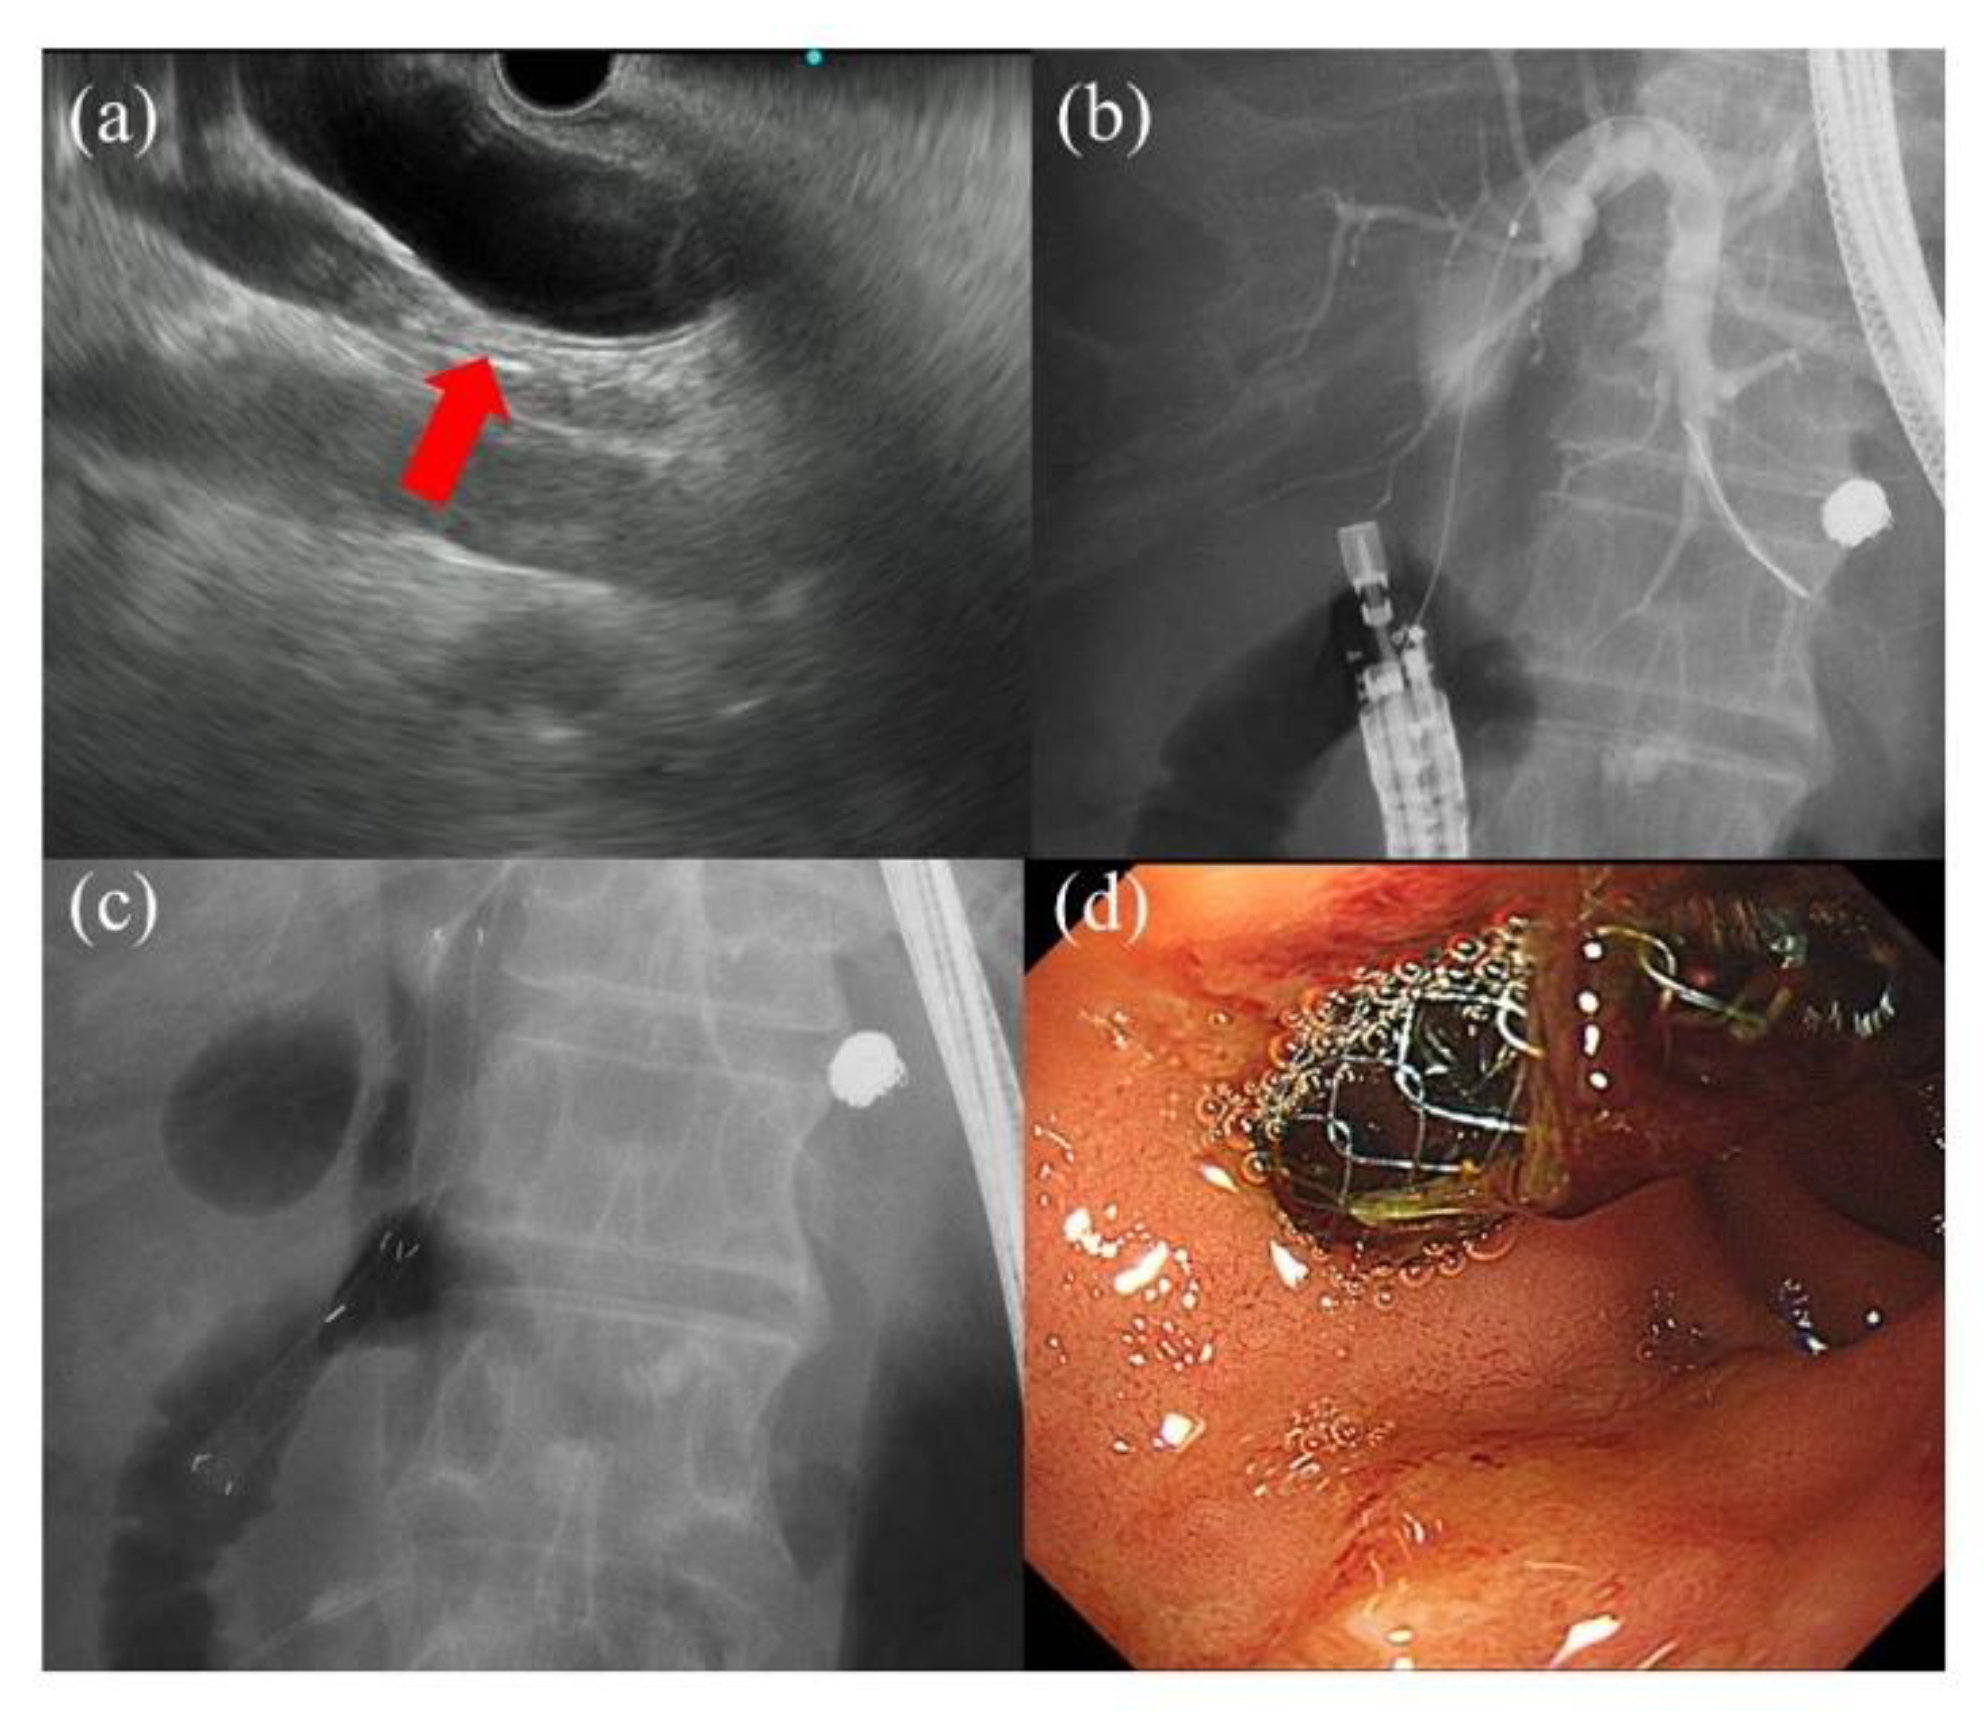

- Hara, K.; Yamao, K.; Niwa, Y.; Sawaki, A.; Mizuno, N.; Hijioka, S.; Tajika, M.; Kawai, H.; Kondo, S.; Kobayashi, Y.; et al. Prospective clinical study of EUS-guided choledochoduodenostomy for malignant lower biliary tract obstruction. Am. J. Gastroenterol. 2011, 106, 1239–1245. [Google Scholar] [CrossRef]

- Song, T.J.; Hyun, Y.S.; Lee, S.S.; Park, D.H.; Seo, D.W.; Lee, S.K.; Kim, M.H. Endoscopic ultrasound-guided choledochoduodenostomies with fully covered self-expandable metallic stents. World J. Gastroenterol. 2012, 18, 4435–4440. [Google Scholar] [CrossRef]

- Kunda, R.; Pérez-Miranda, M.; Will, U.; Ullrich, S.; Brenke, D.; Dollhopf, M.; Meier, M.; Larghi, A. EUS-guided choledochoduodenostomy for malignant distal biliary obstruction using a lumen-apposing fully covered metal stent after failed ERCP. Surg. Endosc. 2016, 30, 5002–5008. [Google Scholar] [CrossRef]

- Lu, L.; Tang, X.; Jin, H.; Yang, J.; Zhang, X. Endoscopic ultrasound-guided biliary drainage using self-expandable metal stent for malignant biliary obstruction. Gastroenterol. Res. Pract. 2017, 2017, 6284094. [Google Scholar] [CrossRef]